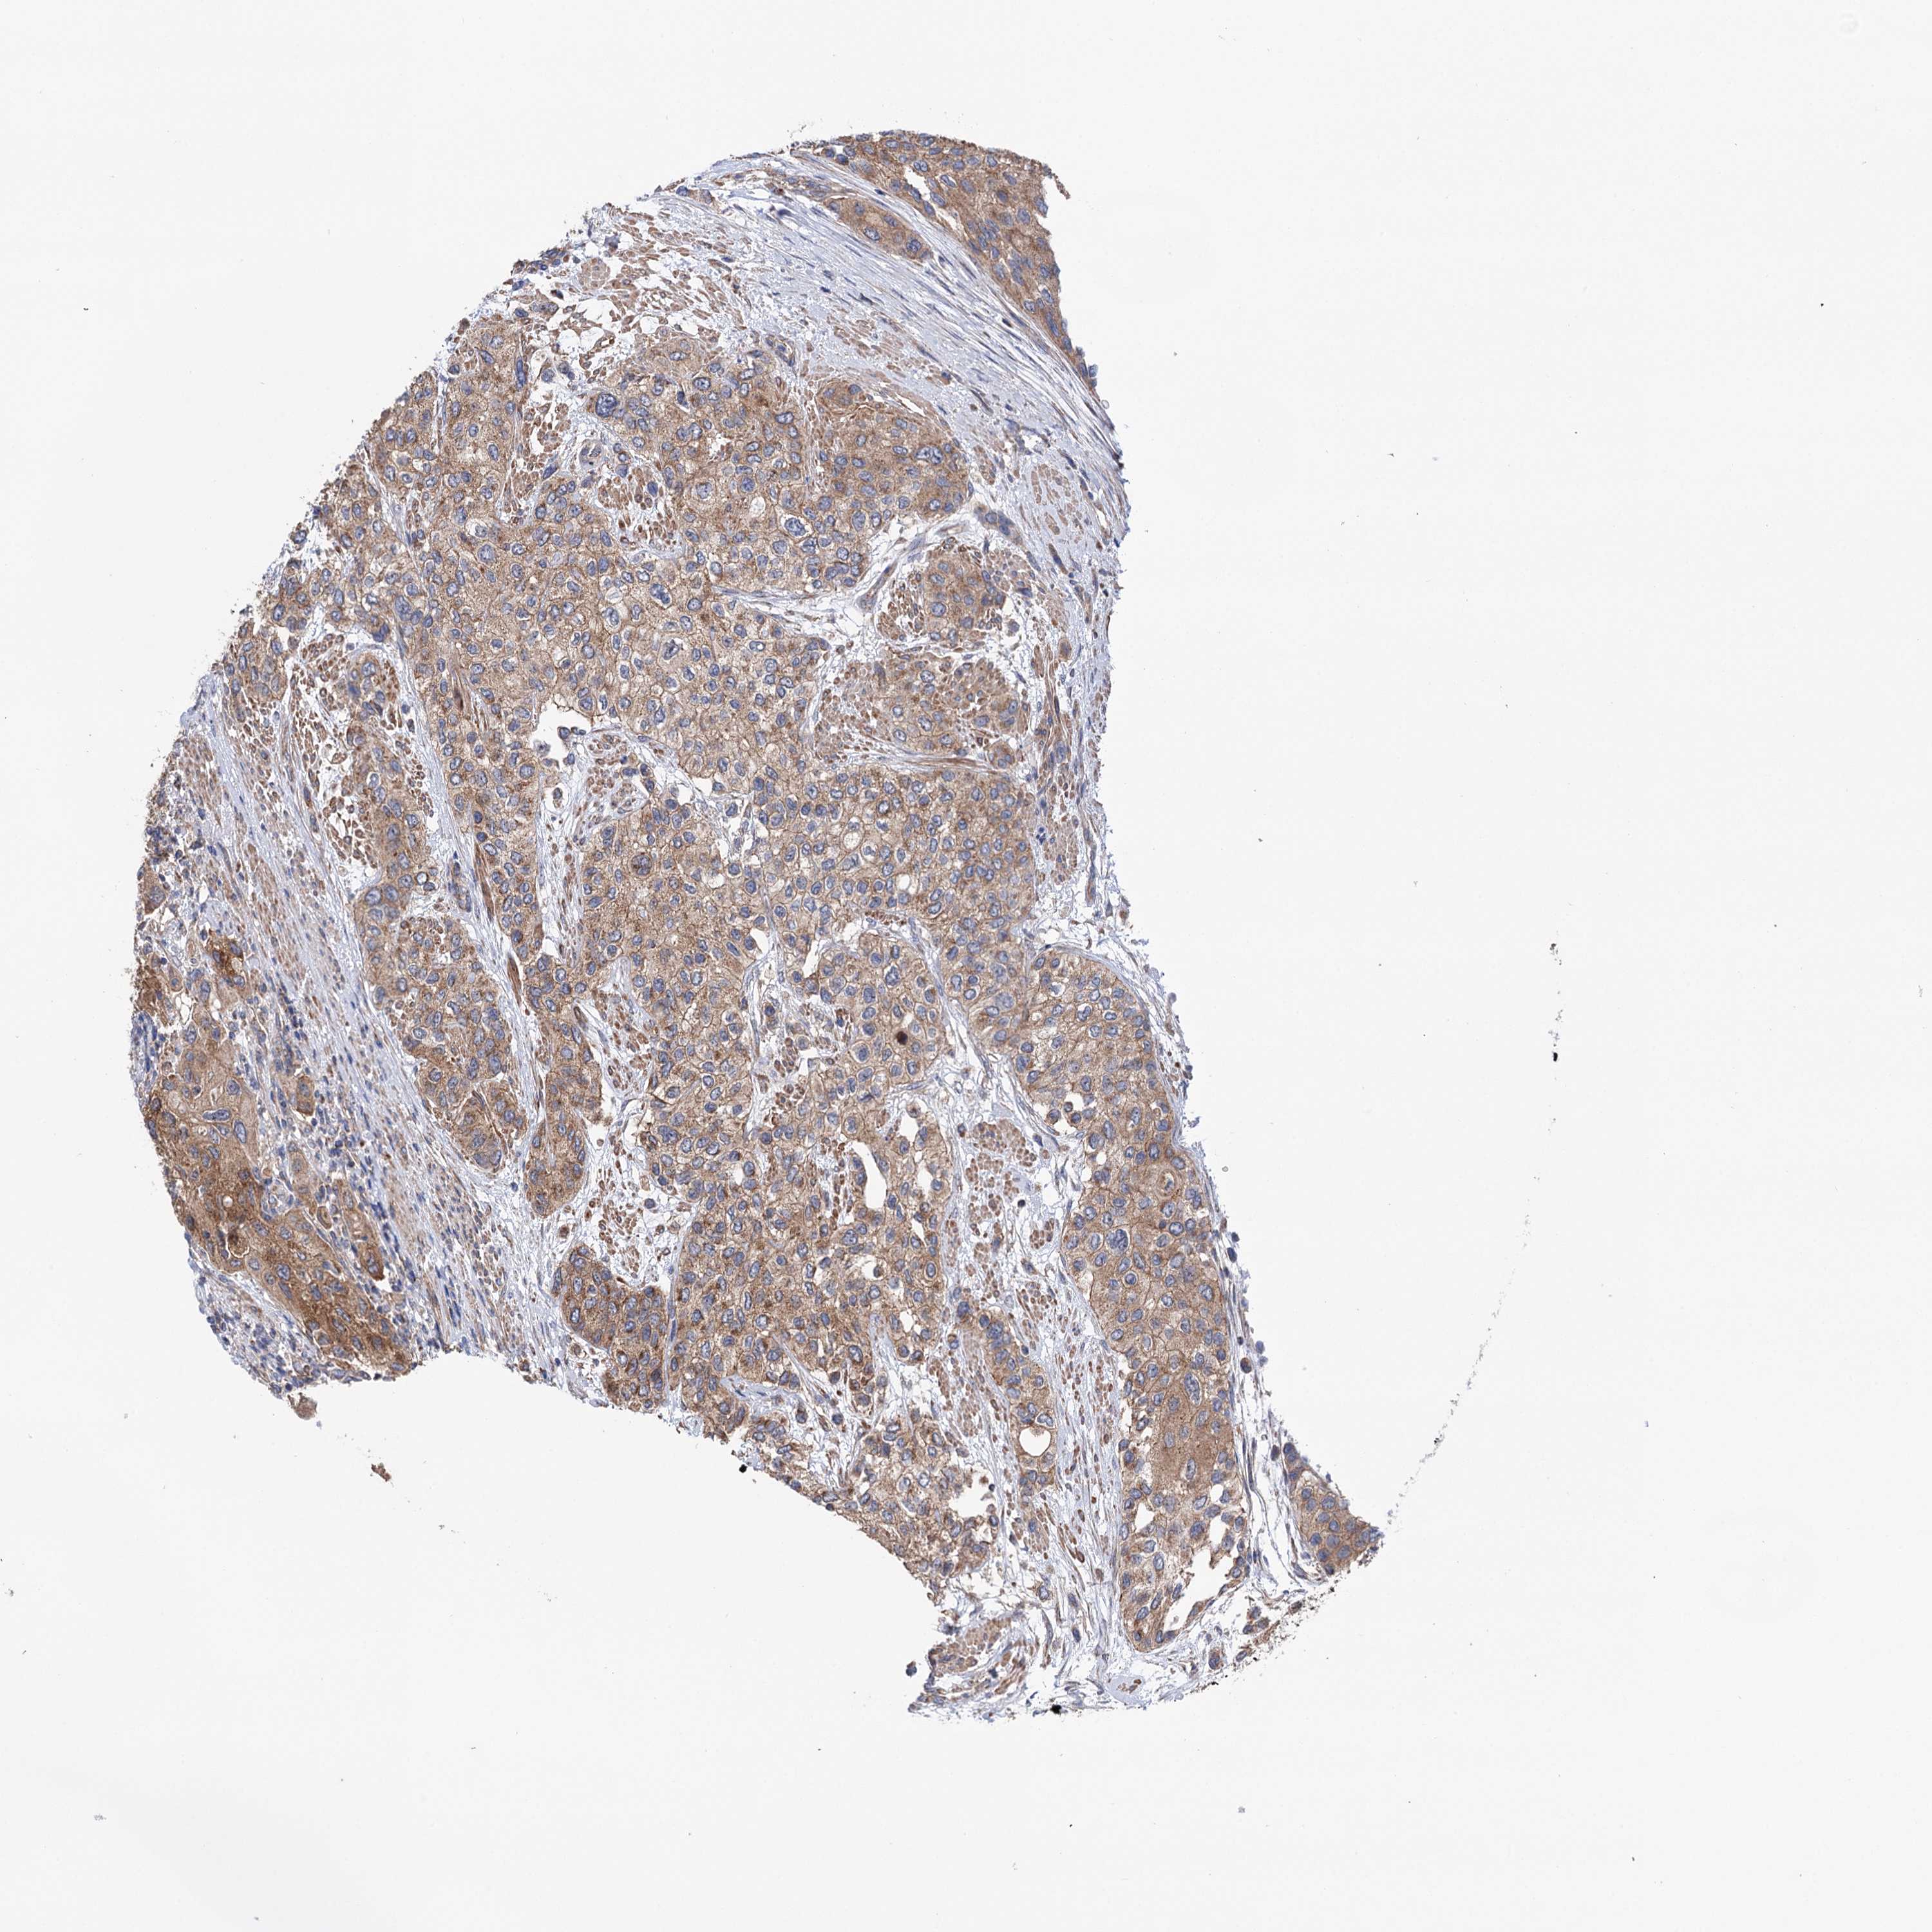

UROTHELIAL CANCER - Protein expressioni

A mouse-over function shows sample information and annotation data. Click on an image to view it in a full screen mode. Samples can be filtered based on level of antibody staining by selecting one or several of the following categories: high, medium, low and not detected. The assay and annotation is described here.

Note that samples used for immunohistochemistry by the Human Protein Atlas do not correspond to samples in the TCGA dataset.

Antibody stainingi

Antibody staining in the annotated cell types in the current human tissue is reported as not detected, low, medium, or high, based on conventional immunohistochemistry profiling in selected tissues. This score is based on the combination of the staining intensity and fraction of stained cells.

Each image is clickable and will lead to virtual microscopy that enables deeper exploration of all samples and also displays staining intensity scores, fraction scores and subcellular localization as well as patient and tissue information for each sample.

Antibody HPA039435

Antibody HPA039536

Antibody HPA061528

Staining

High

Medium

Low

Not detected

Intensity

Strong

Moderate

Weak

Negative

Quantity

>75%

75%-25%

<25%

None

Location

Nuclear

Cytoplasmic/membranous

Cytoplasmic/membranous,nuclear

Urothelial carcinoma, High grade

Urothelial carcinoma, Low grade

Urothelial carcinoma, NOS